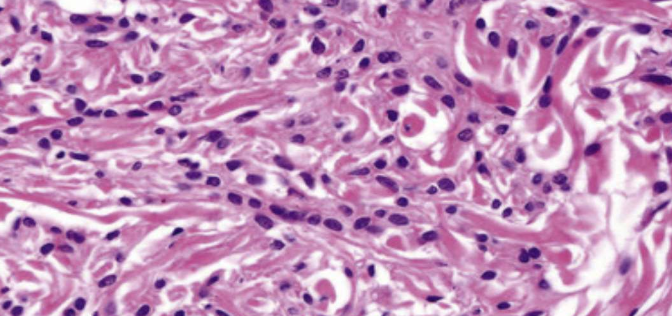

組織

- nonkeratinizing SCC